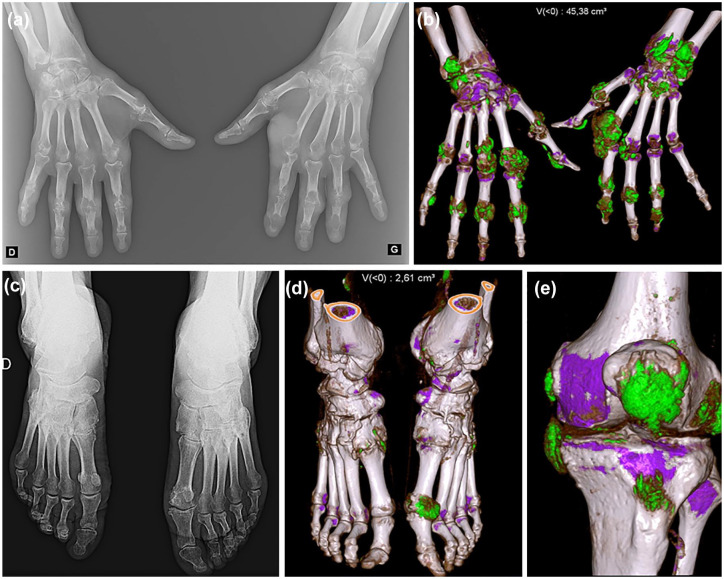

痛风和焦磷酸钙沉积症(CPPD)是晶体性关节炎最常见的病因。确定致病晶体沉积是诊断的基石,同时也是预后和疾病监测的基础。几十年来,传统的放射成像一直是唯一使用的成像技术,但其对这两种疾病的敏感性非常有限。超声波和双能计算机断层扫描(DECT)等先进技术正越来越多地应用于痛风和CPPD疾病的诊断和管理中,它们在分类标准和诊治建议中的作用现已得到广泛认可。在痛风中,单钠尿酸盐沉积的超声基本病变已得到明确定义,并已被证明对变化敏感,可对其进行监测,而 DECT 可对这些沉积物进行直接量化。在 CPPD 疾病中,超声对基本病变的定义及其评分已经非常明确,而 DECT 可以帮助在其他含钙结构中鉴别焦磷酸钙晶体沉积物的概念也已得到证实。本综述旨在概述先进成像技术在晶体诱发的关节病中的应用。

Gout and calcium pyrophosphate deposition (CPPD) disease are the most common causes of crystal arthritis. Identifying the pathogenic crystal deposition is the cornerstone of the diagnosis, but also prognosis and monitoring of the diseases. Conventional radiography has been for decades the only imaging technique used, with its very restricted sensitivity in both diseases. Advanced techniques, namely ultrasound and dual-energy computed tomography (DECT), are being increasingly used in the diagnosis and management of gout and CPPD diseases, and their role is now well recognized in classification criteria and in recommendations for the diagnosis and management. In gout, ultrasound elementary lesions of monosodium urate deposition are well defined and have been shown to be sensitive to change and can be monitored, while direct quantification of these deposits can be performed with DECT. In CPPD disease, the definition of elementary lesions and their scoring has been well established for ultrasound, while the proof of concept that DECT can help discriminate calcium pyrophosphate crystal deposits among other calcium-containing structures has been shown. The aim of this narrative review is to provide an overview of the use of advanced imaging techniques in crystal-induced arthropathies.